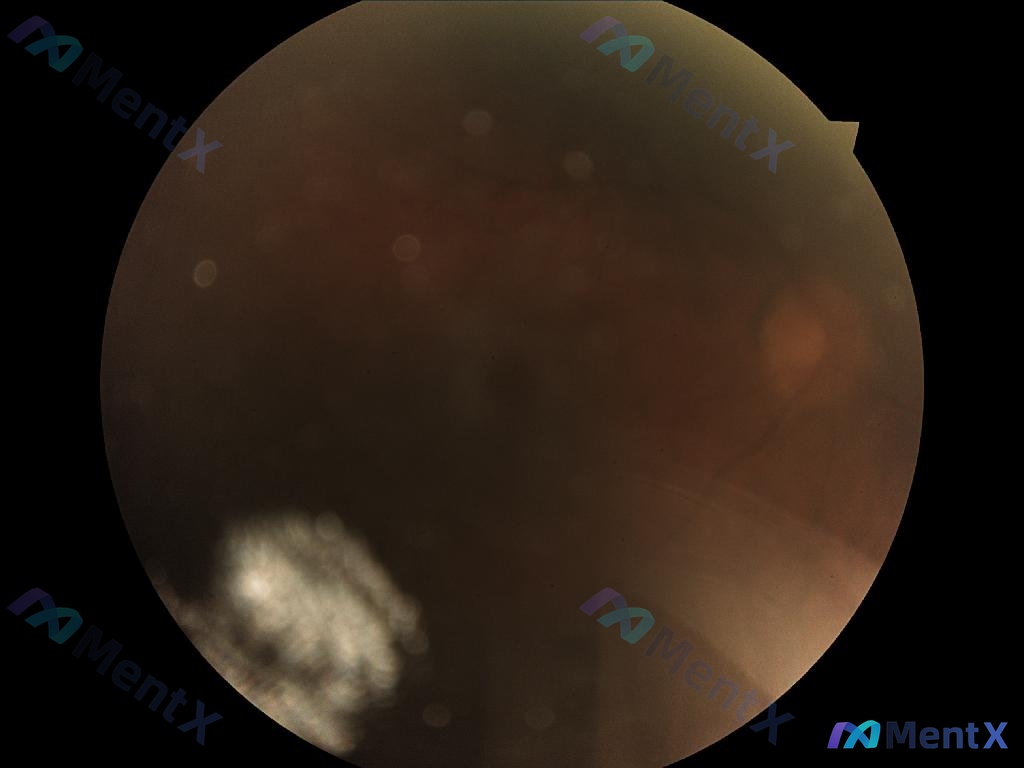

看到一张眼底彩照的分析资料,整理一下思路供大家讨论。 --- 先看影像核心表现 这张图不是“照糊了”,是真的有问题: 1. 整体状态:严重的屈光间质混浊,亮度低,伪影/光晕明显,视网膜深层结构(视盘、黄斑、血管)完全看不见。 2. 玻璃体细节: - 整个视野是弥漫的“烟雾状”或“尘埃状”混浊,提示玻...